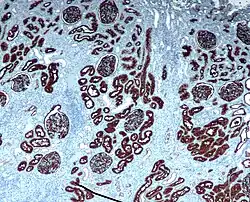

Microscopic cross section of the renal cortex

CD10 immunohistochemical staining of normal kidney. CD10 stains the proximal convoluted tubules and glomeruli.

CD10 immunohistochemical staining of normal kidney. CD10 stains the proximal convoluted tubules and glomeruli. -